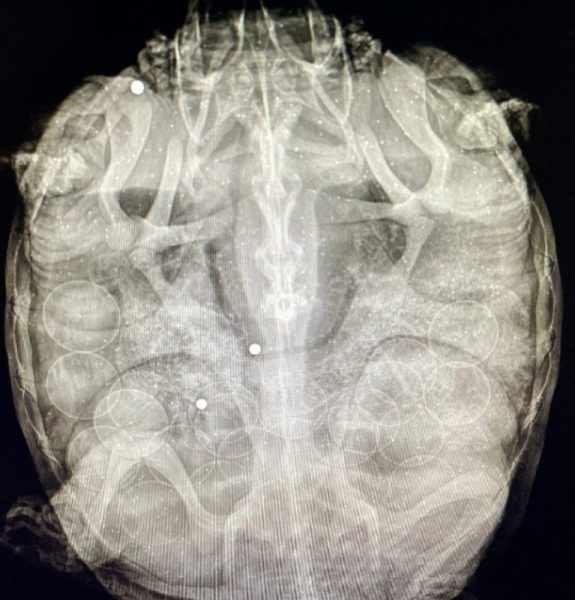

This Snapping turtle patient was brought to the Center after being found with multiple gunshots.

To make matters worse, this is a gravid female (carrying eggs); you can see the eggs in the x-ray below. These adult breeding animals are especially important from a population survival standpoint.

Snapping turtles are a protected species in Virginia. Unfortunately, we see intentional human-caused trauma, including gunshots, every year in this species. Luckily, these gunshot wounds were fresh and only into the bone of the carapace (upper shell). She does not appear to have damaged internal organs. The steel pellets were removed, the wounds cleaned, and pain medications and antibiotics provided.